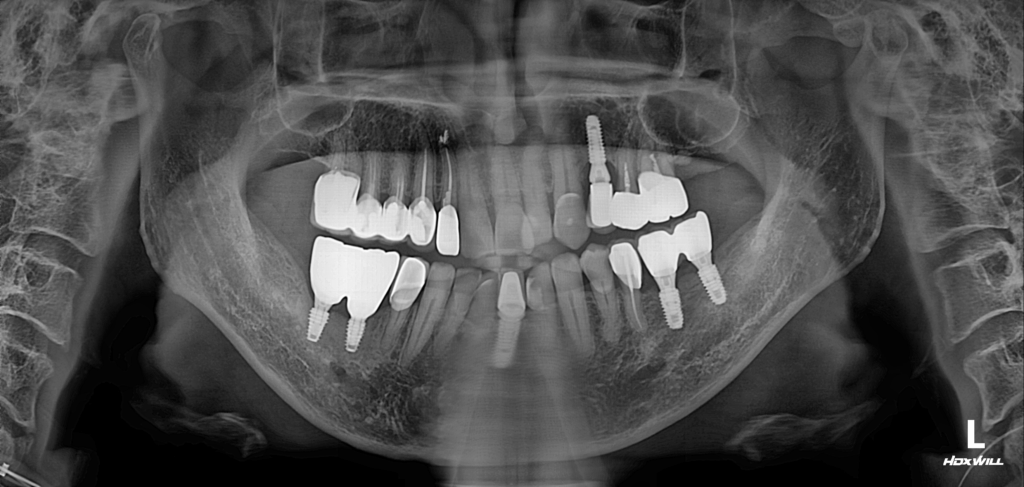

술전 사진

23.04.29

임플란트 재식립은단순히 다시 심는 것이 아니라,처음보다 더 정밀한 진단과세심한 관리가 필요한 치료입니다.잇몸뼈와 주변 조직 상태를 면밀히 확인하고,맞춤형 계획으로 진행한다면 충분히 건강한 기능 회복이 가능합니다. 내원하신 환자분은 우측 하악 임플란트 부위에 불편감을 느껴 검진을 위해 방문하셨습니다.

임상 사진을 확인한 결과, 해당 부위의 잇몸 아래쪽에 염증이 진행되어 있었고, 그로 인해 “골 흡수(뼈 손실)”가 이미 관찰되는 상태였습니다.

이러한 상황에서는 임플란트의 안정적인 기능 회복이 어려워 재식립이 필요한 단계로 판단되었습니다. 이전 의료기관에서 진행된 수술 과정이 크게 잘못된 것은 아니었지만, 보철물의 폭이 지나치게 좁게 설계되어 세균과 음식 잔사가 쉽게 쌓일 수 있는 구조적 한계가 있었던 것으로 보입니다. 이에 따라 임플란트를 보다 적절한 각도로 재식립하고, 보철물 주변에 위생 관리가 용이한 구조로 새롭게 설계하여 재시술을 진행하였습니다.

술후 사진

23.10.26

임상 사진을 살펴보면, 해당 부위의 뼈가 상당 부분 흡수된 상태였기 때문에 영도임플란트 재식립과 함께 골이식이 필요했습니다.

골이식 수술 후 일정 기간 동안치유 과정을 세심히 관찰하며 추후 보철물의 형태를 고려했는데요.아쉽게도 골이식 부위의 회복 속도가 기대보다 더디고, 일부 영역은 충분한 골 형성이 이뤄지지 않는 양상을 보였습니다.

이러한 상태를 종합적으로 판단하여 보철물의 크기와 형태를 조정하고, 저작하는 힘이 균등하게 분산될 수 있도록 하중 설계를 세밀하게 진행했습니다.